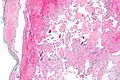

Intravascular papillary endothelial hyperplasia is a rare, benign tumor. It may mimic an angiosarcoma, with lesions that are red or purplish 5-mm to 5-cm papules and deep nodules on the head, neck, or upper extremities.[1][2]: 592